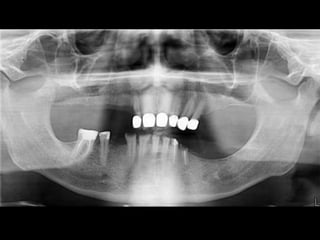

RADIOGRAFÍAS PANORÁMICAS